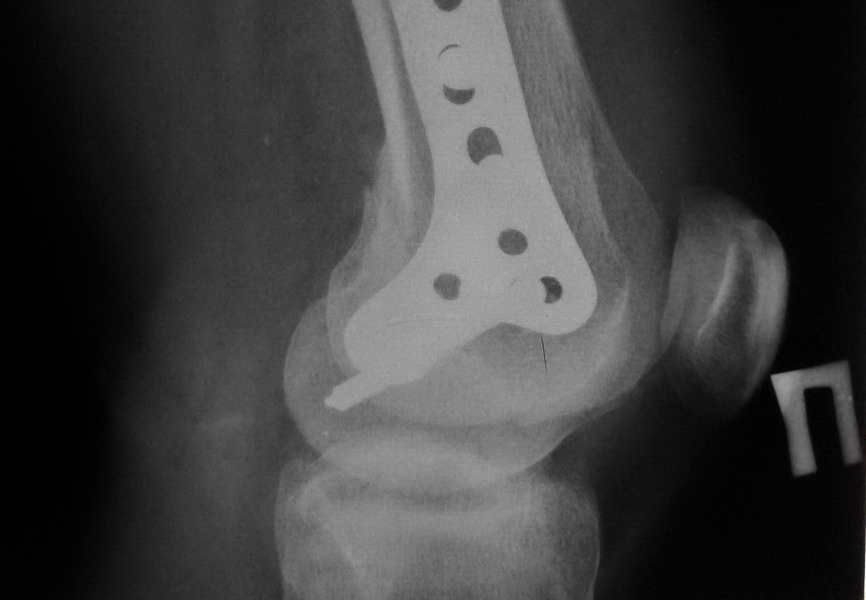

В данном случае предпочтителен парапателлярный доступ, где необходимо создать лучший обзор к мыщелку. После остеотомии и репозиции фиксацию надо проделать поперечными винтами и дополнительно задней antiglade plate - сделанной из 1/3 tubular plate.

Здесь представлены различные варианты фиксации перелома, а также снимки комбинации перелома с повреждением хряща (12-19). Пластика хряща OsseoFit и установка custom made plate.

Остеосинтез LCP пластиной